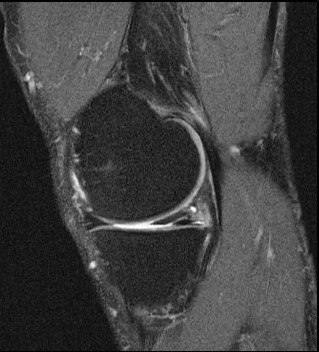

Par opposition au ménisque traumatique, il est question ici de décompensation d’un ménisque-maladie ou de lésion méniscale dégénérative, associée au vieillissement du tissu méniscal. Le ménisque est usé, un clivage horizontal dégénératif en découle (fig. 1), et ce clivage fragilise le ménisque, qui peut alors se casser, se fissurer, sans traumatisme. Il faut se poser la question de l’éventuelle arthrose associée afin de déterminer d’où provient la douleur : du ménisque, du cartilage, des deux ?

La figure 1 montre l’IRM d’une lésion méniscale dégénérative typique du sujet d’âge mûr ; il s’agit d’un exemple de découverte fortuite, le patient étant asymptomatique.